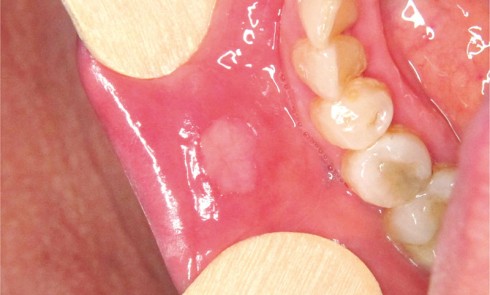

Article réservé à nos abonnés Ulcérations orales d’origine traumatique et iatrogène

Après l’aphte, les ulcérations les plus fréquentes sont de causes traumatiques ou iatrogènes. Elles sont à rechercher au cours de...